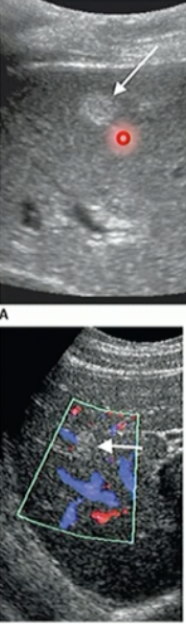

Difference between Haemangioma + HCC

Haemangioma has no blood vessels/lack of

HCC has blood vessels/blood flow

Pathology?

Haemangioma (due to no colour on it)

HCC due to colour/bloodflow